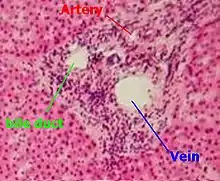

The Liver & Portal System